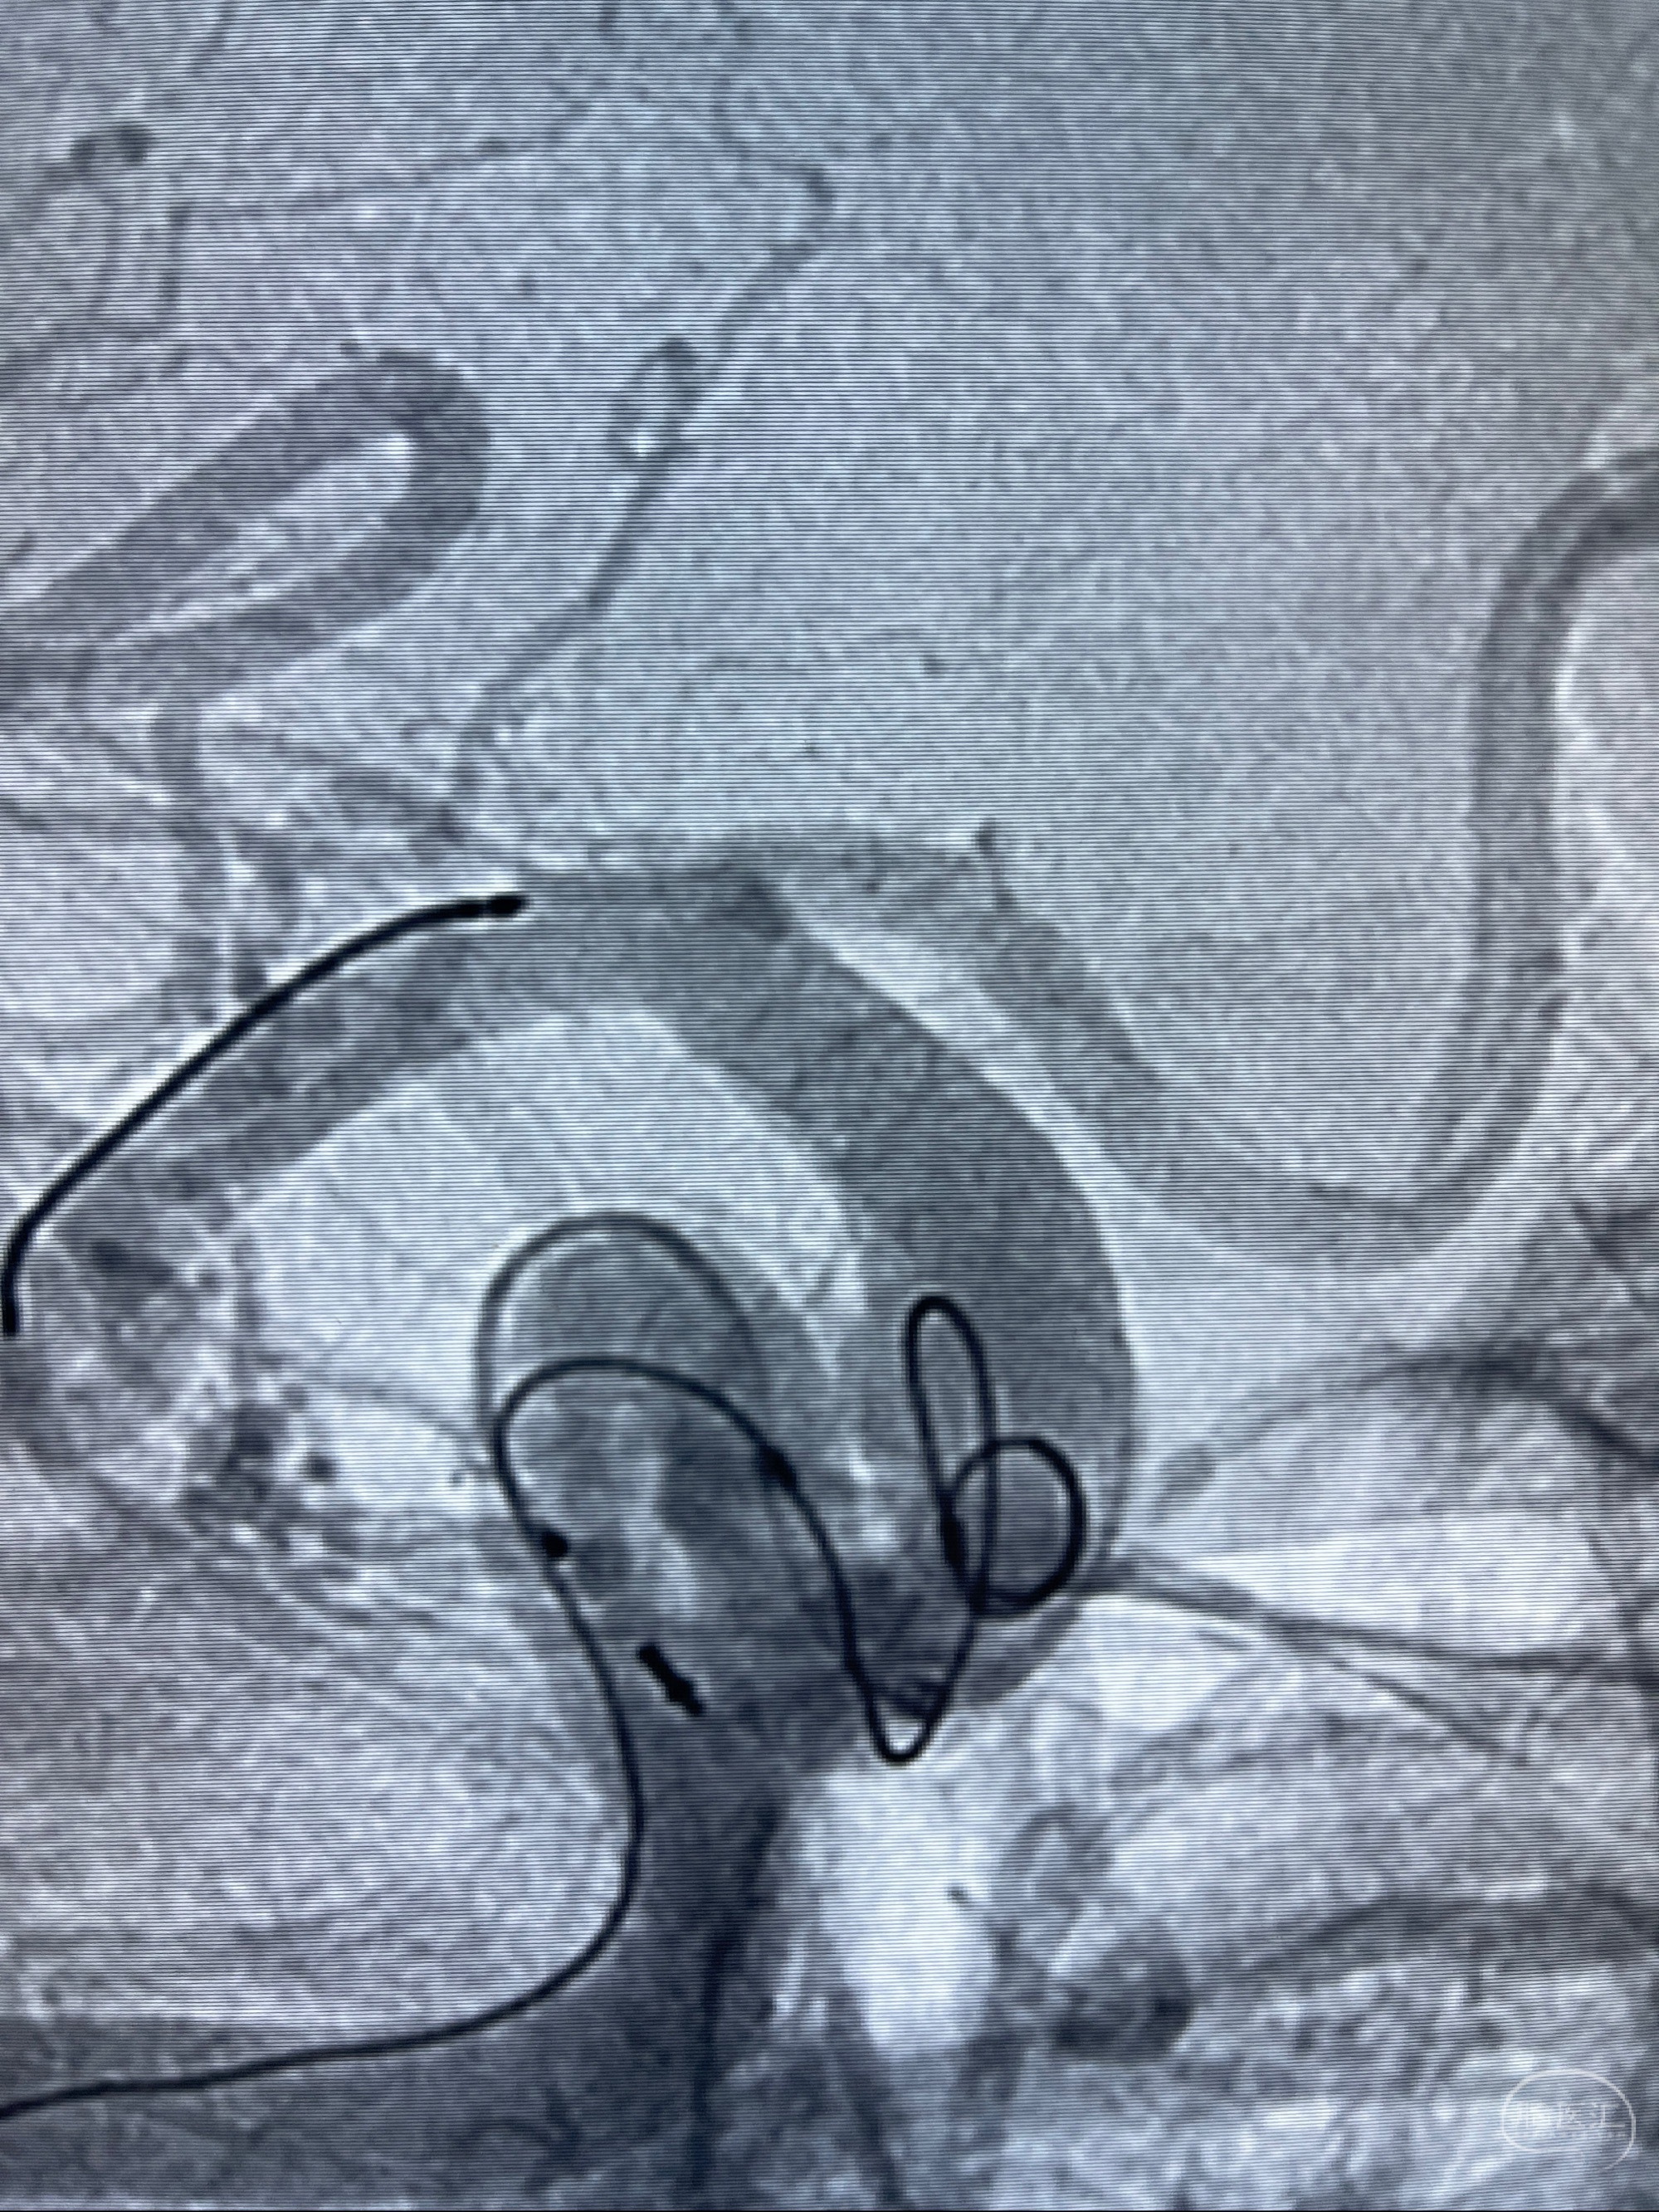

2023-07-27全脑血管造影:双侧颈内动脉眼动脉段动脉瘤,右侧较大

2023-08-01全麻下行双侧颈眼动脉瘤支架辅助栓塞

- pipeling4.5-20mm

- pipeline 4.0-20mm